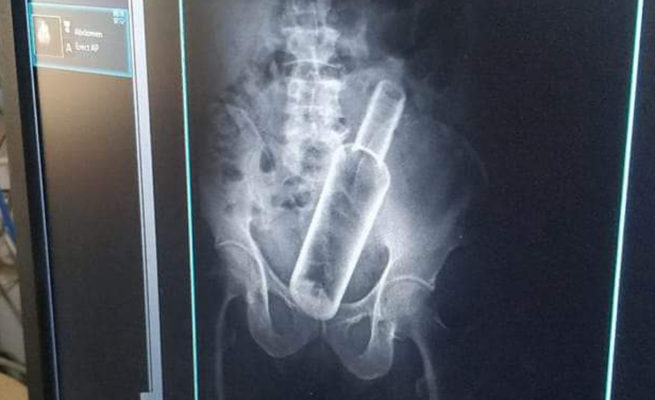

धनगढी । सेती प्रादेशिक अस्पतालमा उपचार गर्न गएका एक वृद्धको पेटमा बोतल भेटिएको छ । धनगढीको फूलबारी बस्ने ६१ वर्षीय जमनसिंह रोकामगरको एक्सरे गर्दा पेटमा रक्सीको बोतल देखिएको अस्पतालले जनाएको छ । प्रादेशिक अस्पतालका सूचना अधिकारी मेखराज उपाध्यक्षले दिएको जानकारी अनुसार बिहीबार पेट दुखेपछि अस्पताल आएका रोकामगरको एक्सरे गर्ने क्रममा बोतल देखिएको हो ।

उनकाअनुसार केही दिनअघि मदिरा सेवन गर्ने क्रममा साथीले मलद्वारबाट बोतल पेटमा घुसाइदिएको बताएका छन् । उनको प्रादेशिक अस्पतालमा उपचार भइरहेको छ ।